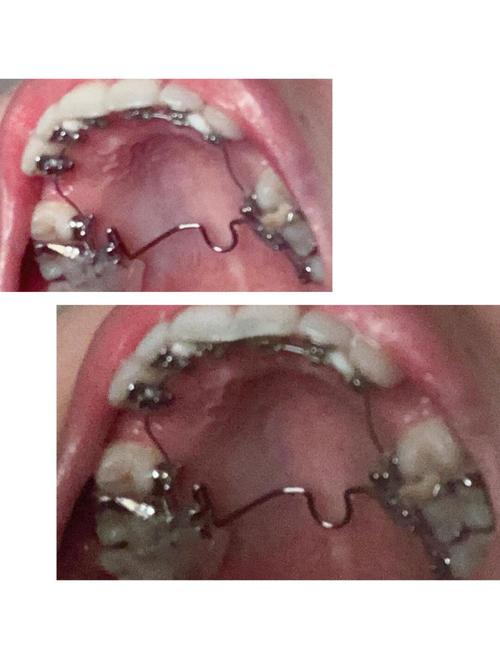

- 个性化定制: 每一颗牙齿的舌侧托槽都是根据患者牙齿的精确三维模型,通过计算机辅助设计和制造技术(CAD/CAM)个性化定制的,托槽的底座与牙齿舌侧表面完美贴合,弓丝也是根据牙齿移动路径精确弯制的。

- 个性化托槽与弓丝制造: 利用CAD/CAM技术,根据设计方案为每颗牙齿定制舌侧托槽,并制造一系列用于不同矫治阶段的个性化弓丝。

- 间接粘接: 这是最关键的技术之一,医生在模型上预先将所有托槽精确粘接到牙齿舌面的理想位置,然后制作一个转移托盘,复诊时,利用转移托盘将托槽一次性、精确地转移到患者口内,大大提高了粘接效率和准确性,减少了椅旁操作时间。

- 复诊调整: 定期复诊(通常4-8周一次),医生更换更粗或形态更复杂的弓丝,施加矫治力,引导牙齿按计划移动,每次调整可能比唇侧更耗时。

- 保持: 矫治结束后,需要佩戴保持器,舌侧矫治通常推荐使用舌侧保持丝(粘接在牙齿舌侧)配合透明压膜保持器(戴在牙齿外面)或舌侧保持器,以维持矫治效果。